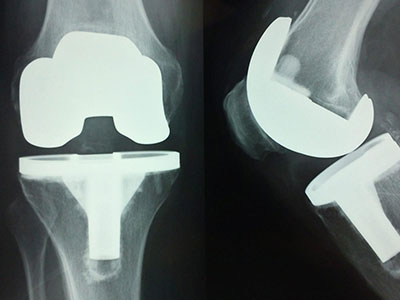

We specialize in advanced Joint Replacement surgeries, including complex primary and revision procedures. Our team also offers expert care in spine surgery, arthroscopy, limb reconstruction, and pediatric orthopedics — all under one roof.

• Advanced Joint Care

Expert orthopedic treatments for joint pain, arthritis, and knee/hip replacement surgery using minimally invasive techniques.